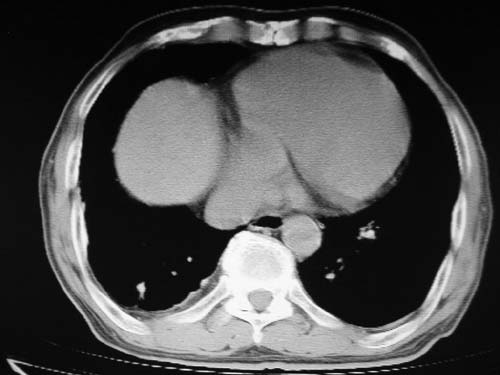

男,80岁

肺动脉段突出,左右肺门不等大,左肺门明显增大,肺动脉干及左肺动脉明显增宽,考虑先天性肺动脉狭窄瓣膜狭窄型。

)考虑肺动脉扩张,右心室增大,主动脉弓段正常位弓后段明显变小(不会是动脉导客未闭吧,不知患者有何症状病史)0。2)右肺上叶继发性肺结核。3)右侧胸膜增厚、钙化,左侧胸膜反应。

肺动脉高压,左肺动脉瘤样扩张。